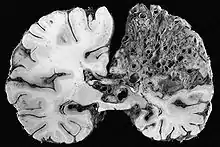

Neuropathology

Neuropathology is the study of disease of nervous system tissue, usually in the form of either surgical biopsies or sometimes whole brains in the case of autopsy. Neuropathology is a subspecialty of anatomic pathology, neurology, and neurosurgery. In many English-speaking countries, neuropathology is considered a subfield of anatomical pathology. A physician who specializes in neuropathology, usually by completing a fellowship after a residency in anatomical or general pathology, is called a neuropathologist. In day-to-day clinical practice, a neuropathologist is a consultant for other physicians. If a disease of the nervous system is suspected, and the diagnosis cannot be made by less invasive methods, a biopsy of nervous tissue is taken from the brain or spinal cord to aid in diagnosis. Biopsy is usually requested after a mass is detected by medical imaging. With autopsies, the principal work of the neuropathologist is to help in the post-mortem diagnosis of various conditions that affect the central nervous system. Biopsies can also consist of the skin. Epidermal nerve fiber density testing (ENFD) is a more recently developed neuropathology test in which a punch skin biopsy is taken to identify small fiber neuropathies by analyzing the nerve fibers of the skin. This test is becoming available in select labs as well as many universities; it replaces the traditional nerve biopsy test as less invasive.